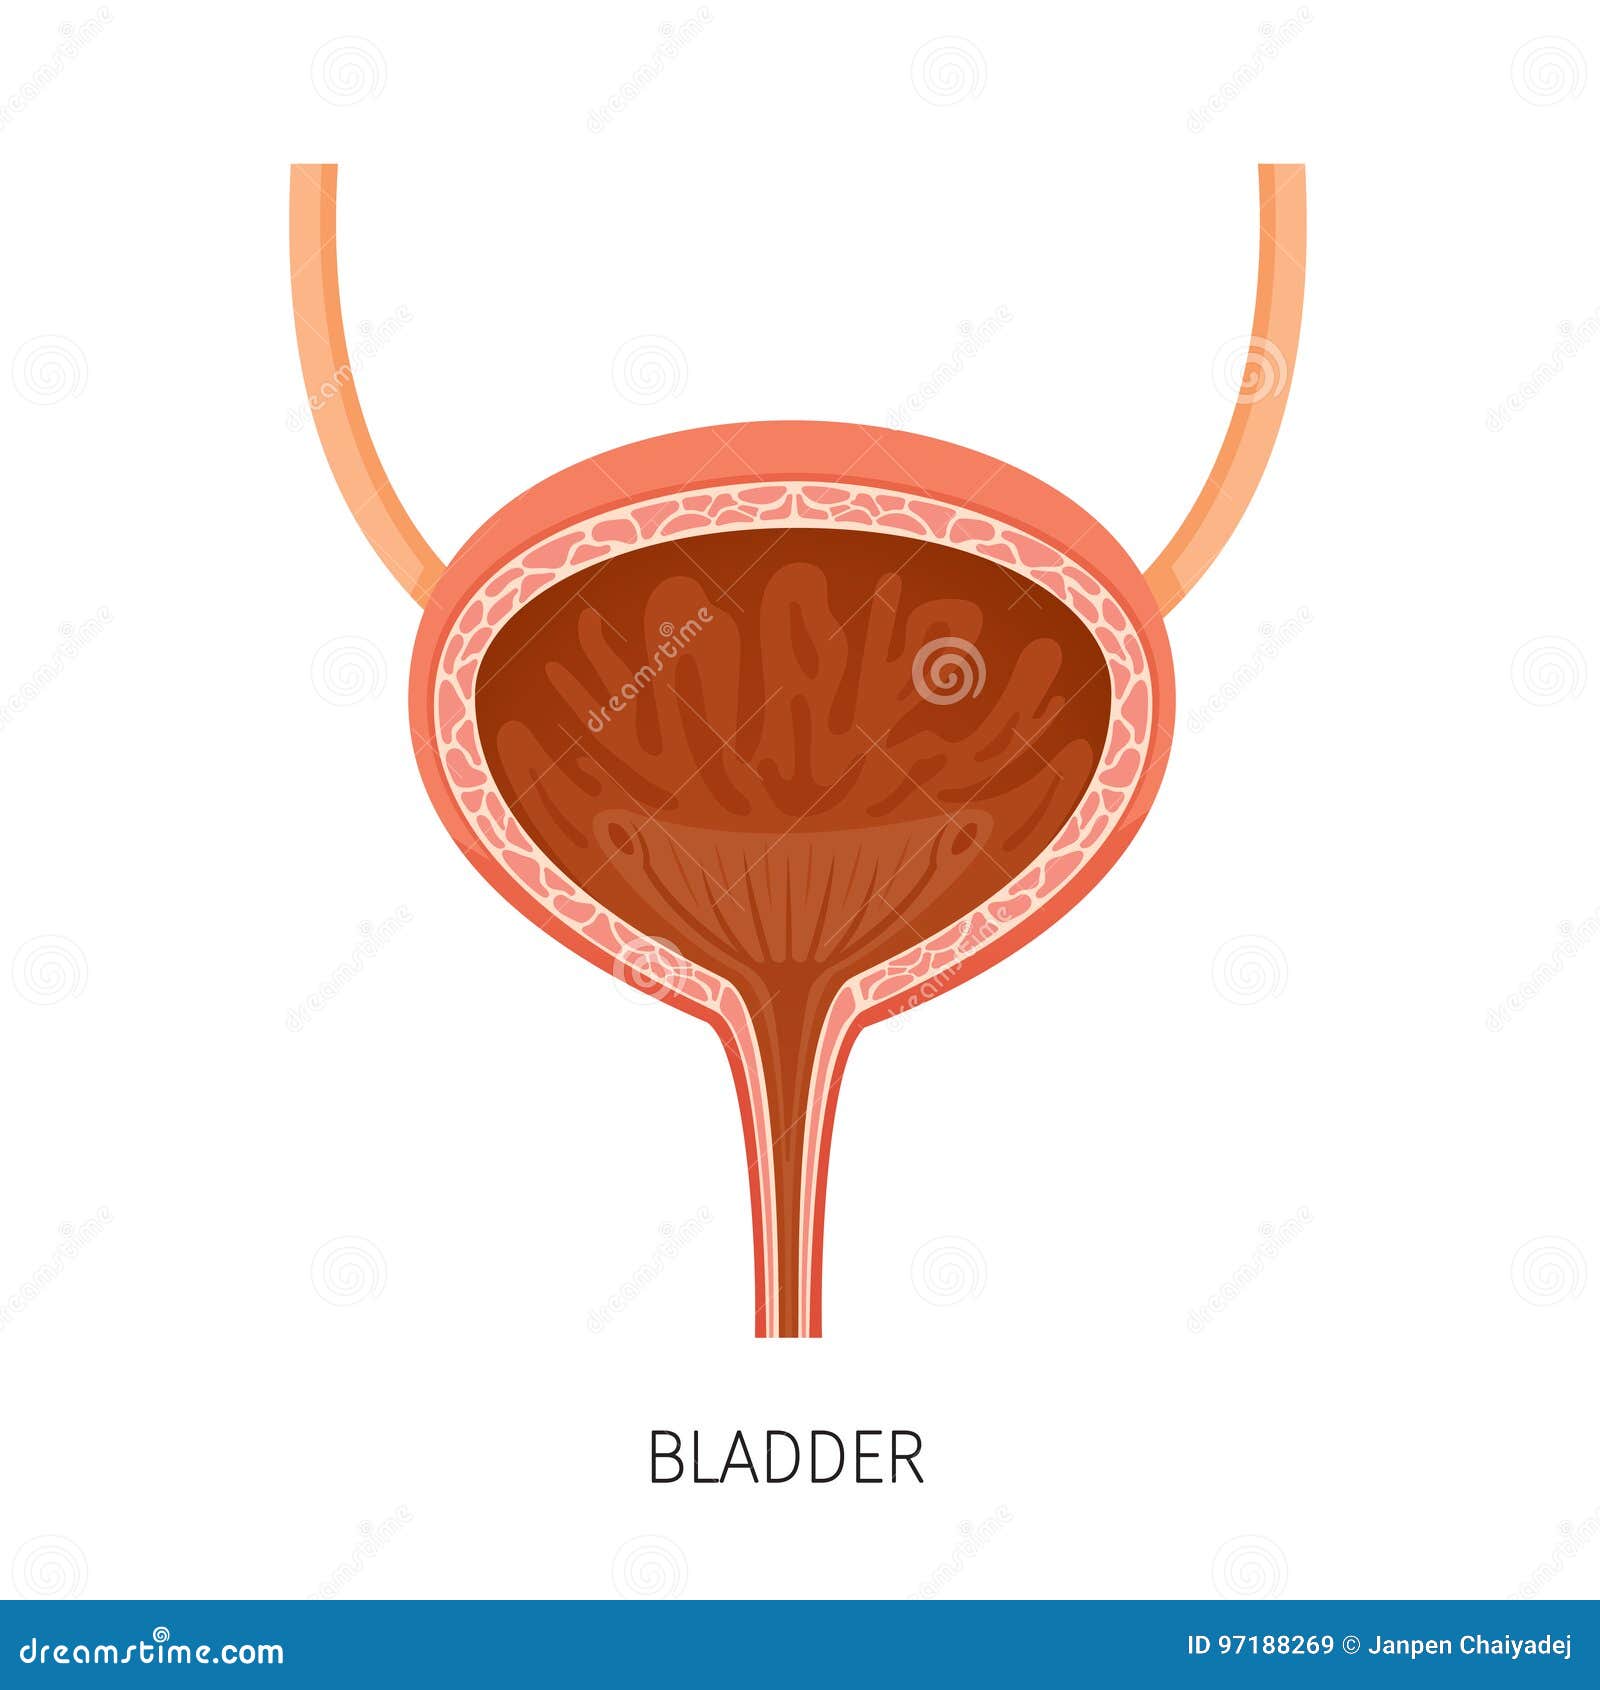

location of the bladder in the human body

Posts: location of the bladder in the human body